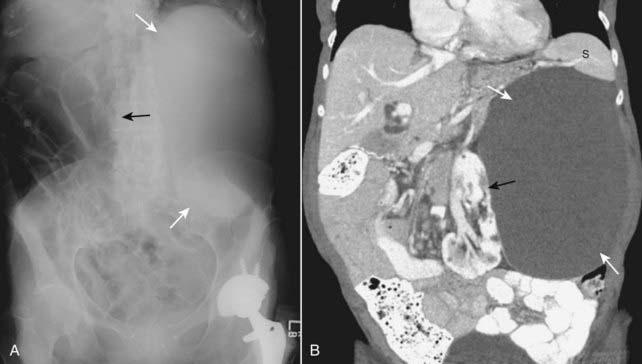

Figure 13-24 Enlarged kidney.

Soft tissue masses or organomegaly can be diagnosed from a conventional radiograph either by visualizing the edge of the mass if there is fat or air surrounding it or by displacement of bowel. A, On the conventional radiograph, there is a soft tissue mass in the left upper quadrant (solid white arrows), which is displacing bowel to the right (solid black arrow). B, A coronal reformatted CT scan of the same patient demonstrates a large renal cyst (solid white arrows) arising from the left kidney (solid black arrow), displacing it and the surrounding bowel. The cyst is compressing the spleen (S).